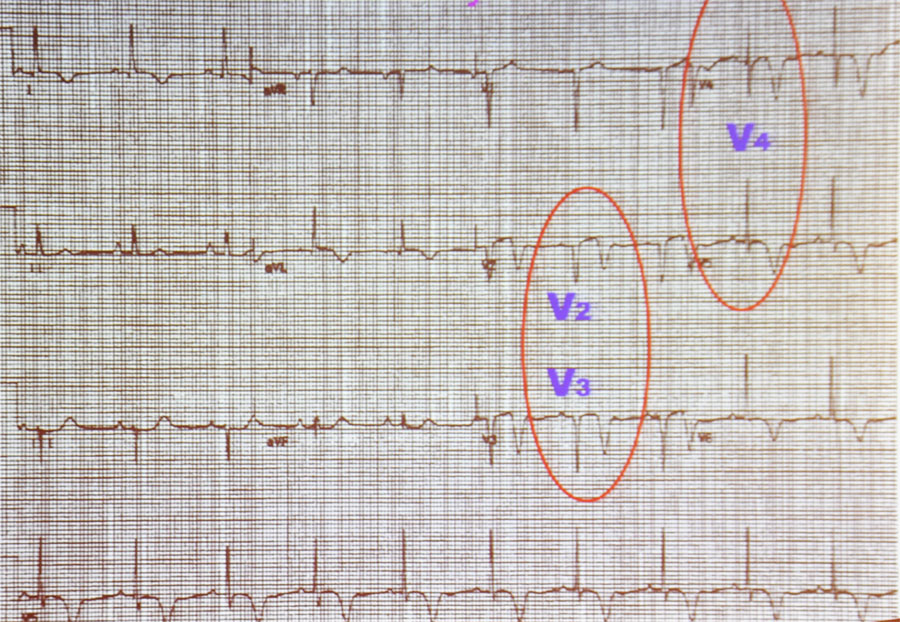

否认糖尿病与高血>压病史,急查心电图(图4a)示窦性心律,t波改>变(tv1>

患者入院心电图检查结果 胸前导联广泛t波倒置